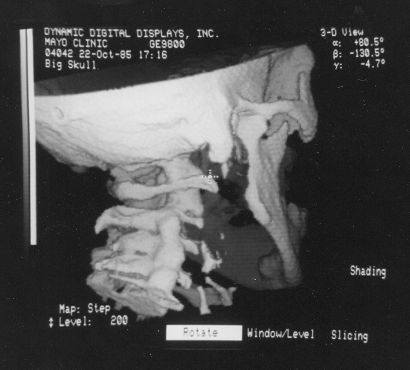

These photos of the Voxelscope II screen are typical of the types of rendering provided by the system.

Voxelscope II Screen Shots. Combination of 3-D Shaded Surface, Multiplanar Reformatting, and Segmentation